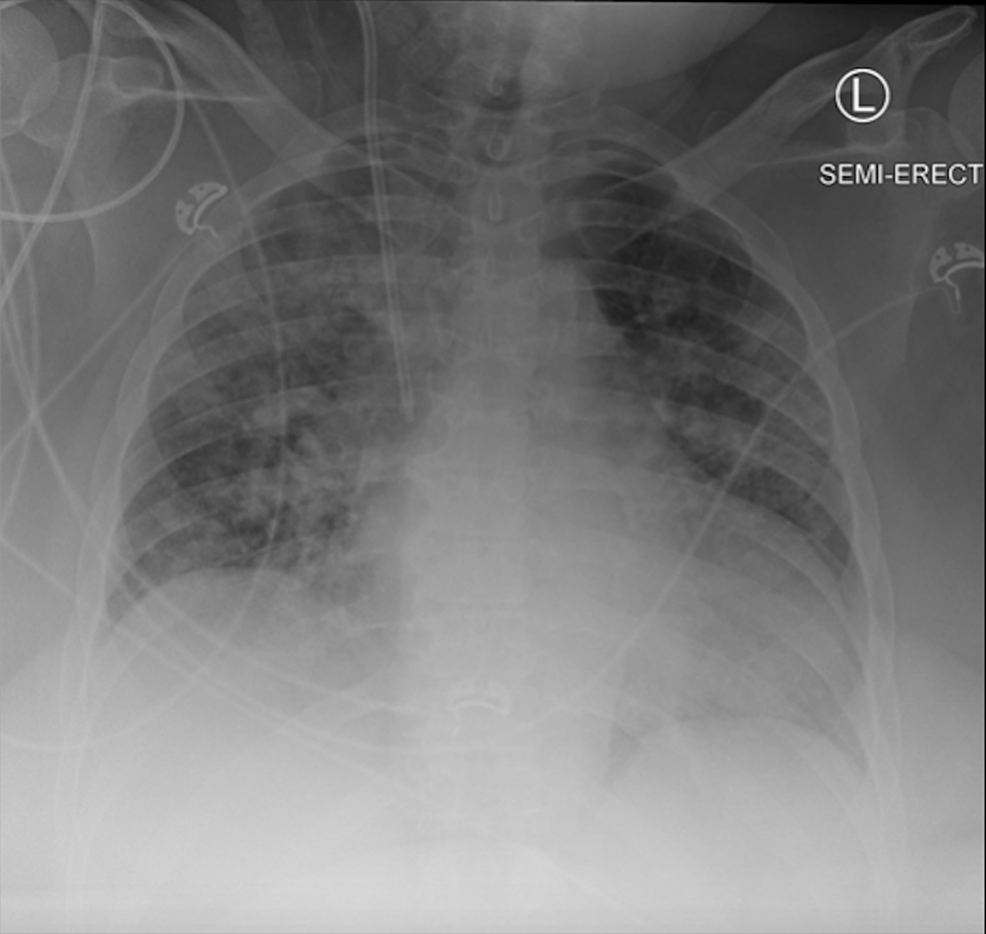

The combined risk of the uncertain validity of external COVID-19 tests, the severe symptomatic nature of the patient, and the vulnerable burn unit patient population prompted the decision to order a third, internal, COVID-19 test, and to obtain an additional CXR (Figure 2).